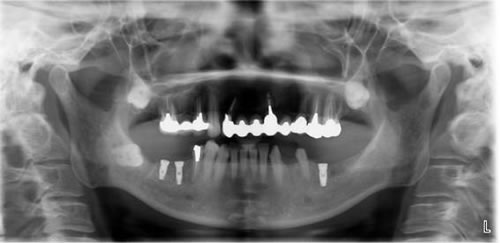

術後のエックス線です。

After